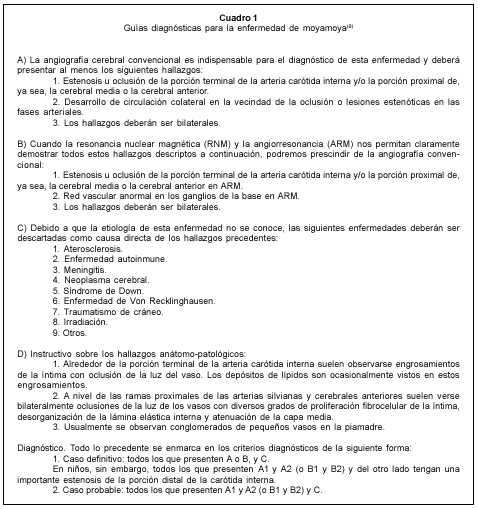

La resonancia magnética (RM) puede dar claves que orienten al diagnóstico, como ser: en T1, múltiples imágenes punteadas de vacío de señal en los ganglios basales que realzan con gadolinio; en T2, hiperseñal de los pequeños vasos, infartos corticales o de sustancia blanca; y en FLAIR, surcos hiperintensos debidos a la disminución de flujo en los vasos piales y al engrosamiento de las membranas aracnoidales. El realce leptomeníngeo en T1 con gadolinio normalmente disminuye luego de una cirugía efectiva. Por otro lado, la RM es de gran utilidad para identificar áreas de isquemia o hemorragia y evaluar su tiempo de evolución. Debido al progreso de las técnicas de este tipo, el comité de investigación de la enfermedad del Ministerio de Salud y Bienestar de Japón ha realizado estudios comparativos ente la angiografía digital y la angiorresonancia magnética (ARM). Las conclusiones de estos estudios demuestran que el diagnóstico de moyamoya puede realizarse prescindiendo de la angiografía convencional si se cuenta con las técnicas de ARM más avanzadas(16). El mismo ministerio publicó en 1996, en inglés, las guías diagnósticas para esta enfermedad (cuadro 1). El haber creado pautas diagnósticas universalmente aceptadas permite la unificación de criterios en cuanto a la enfermedad(17). Estas guías no solo se utilizan para el diagnóstico, sino también para el seguimiento de pacientes y para la realización de investigaciones en el tema.